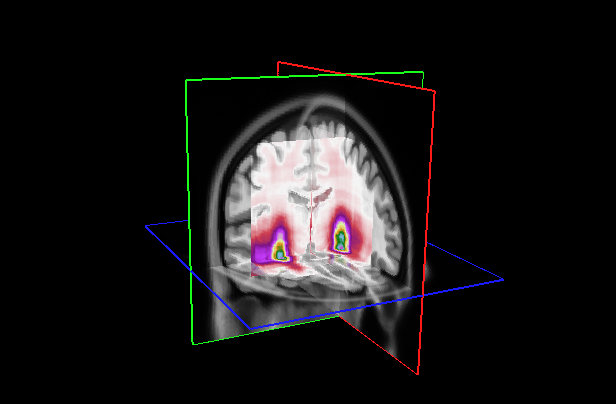

Figure 7: (Left) Attention distribution for each plane averaged on all the five test to provide entire dataset distributions; (Right) Visualization of mean 3D attention map of entire dataset overlapped to MNI152 template

This section analyzes the interpretability of our approach and those proposed in (Wang et al., 2024; Altay et al., 2021). Our XAI method described in Section 4.3 allowed us to produce a 3D attentional map starting from the attentional weight distributions of the axial, coronal, and sagittal planes. The authors of AwareNet (Wang et al., 2024) designed the slice-aware module of this network to extract, as in our case, a distribution of attentional weights capable of summarizing the importance of each slice in the decision-making process. As a result, our approach can produce a 3D map also using the model proposed in (Wang et al., 2024).

This subsection examines the visual results and quantitative analysis concerning the brain areas emphasized by each model. Fig. 7, on the left, displays the attentional weight distributions across the three planes, averaged over all five folds of the cross-validation. This averaging provides a comprehensive view of the data distribution across all images in the dataset. Starting from the entire dataset distributions, the 3D attentional map was created as detailed in Section 4.3. The averaged 3D map was enhanced by a factor of 10 and overlaid on the MNI152 template, which is representative of a typical patient’s brain. Combining this template with its corresponding atlas facilitates the identification of regions that, on average, received attention from the models. The right side of Fig. 7 shows the explainable MRI generated. The visual representation also indicates that the network targets the medial temporal lobe region, as suggested by the distributions. This result is confirmed by the quantitative analysis shown in Table 8, which reports the metrics for the 20 more extensive regions selected by our model and by AwareNet. As shown in Table 8(a), the three largest regions focused by our diagnosis model are the hippocampus, the parahippocampus, and the amygdala. In contrast, the 3D attentional map generated with AwareNet appears to focus on different regions. The first 3 regions highlighted are Cerebellum Gray Matter, Lateral Occipital, and Fusiform. The right part of the hippocampus appears only after them. From this result, it is also possible to note that with the same 99.9 percentile threshold for binarization, our model highlights a much more localized region. Specifically, our model selects 17 regions with a strong concentration in the top 14. On the contrary, AwareNet highlights 88 regions, 68 of which have been omitted in the Table 8.